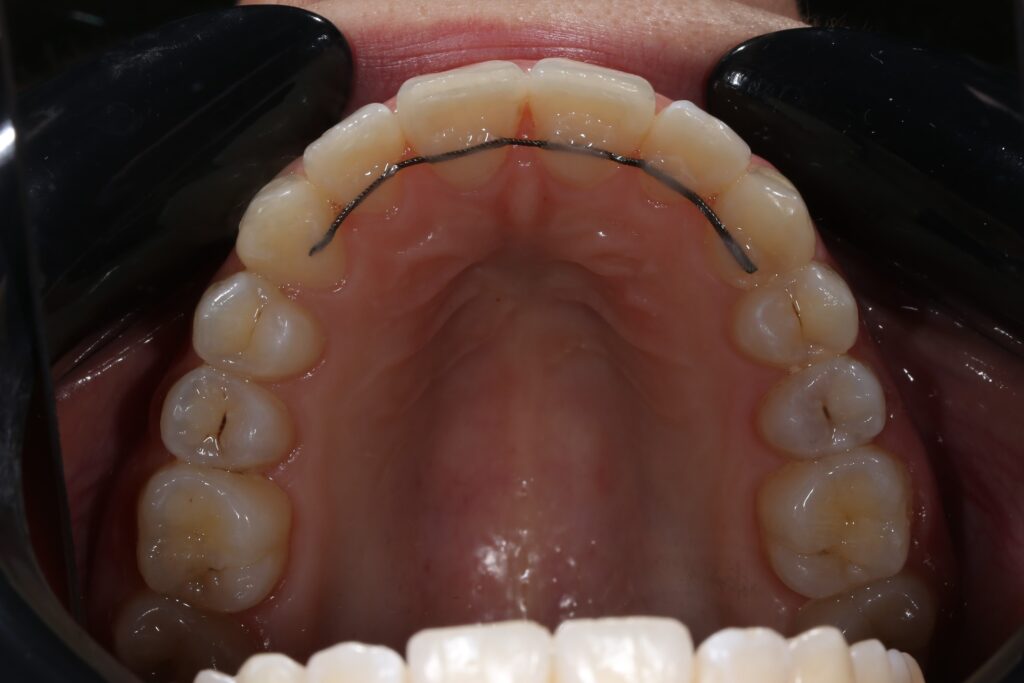

Результат

Была установлена брекет-система Damon Q.

пациент после ортодонтического лечения